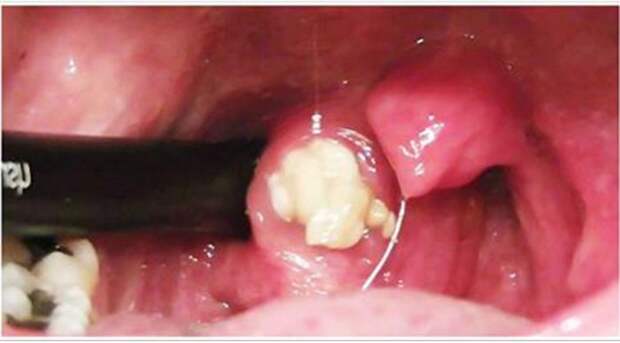

Это желто-белые комочки творожистой консистенции с очень неприятным запахом, которые, как правило, образуются в результате хронического воспалительного заболевания глотки и миндалин — тонзиллита.

Видеоролик ниже — не для слабонервных. Это демонстрация того, сколько всего может скрываться в лакунах миндалин.